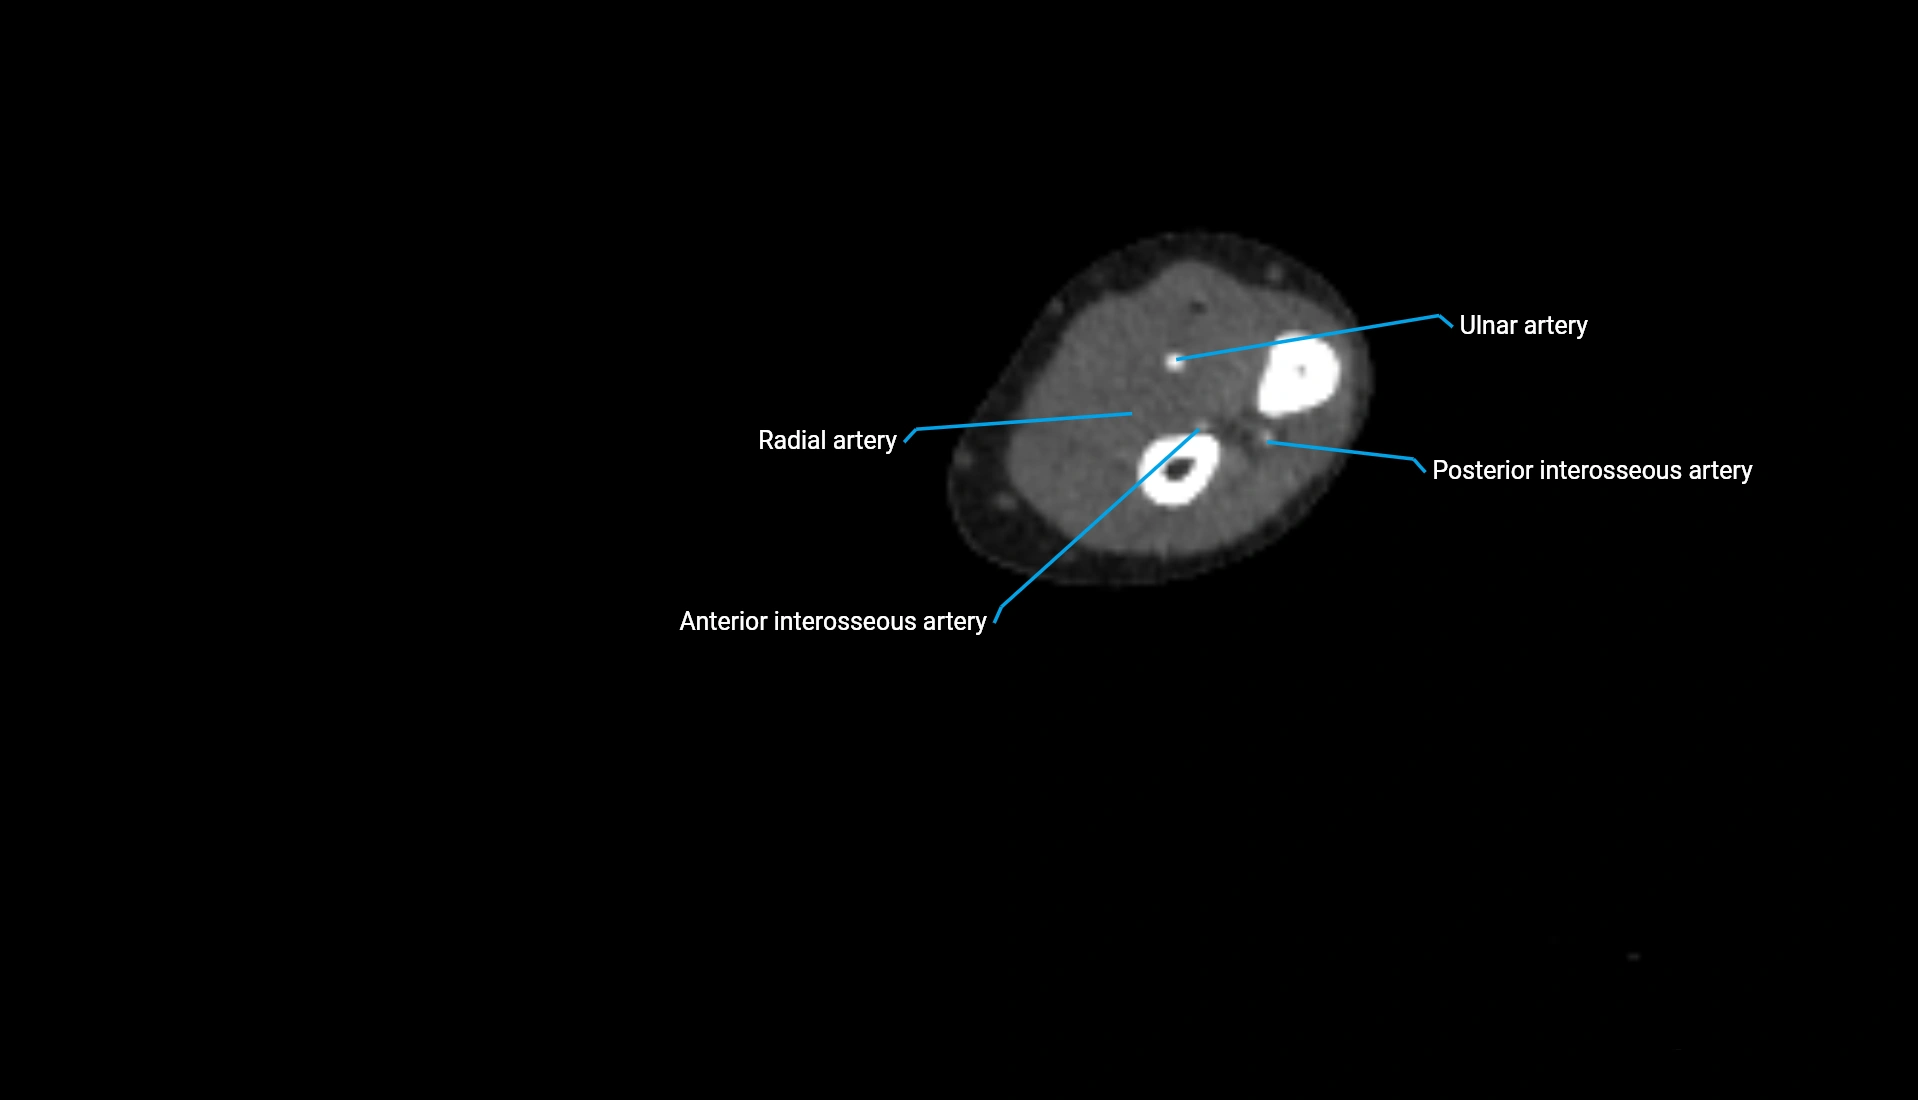

MRI image

image